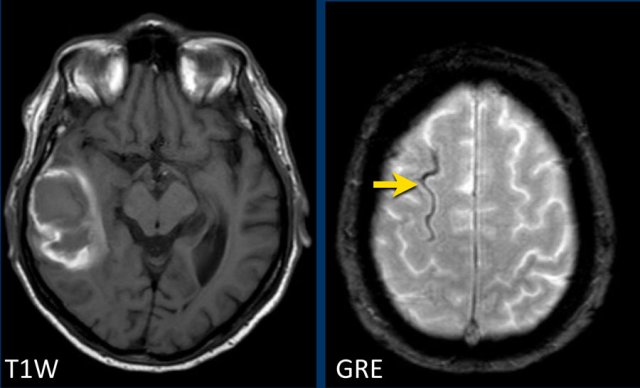

Cortical superficial siderosis in CAA

CAA-related bleeds include:

• Macrobleeds - symptomatic lobar hemorrhages

• Microbleeds - small and typically silent peripherally located

• Cortical superficial siderosis (cSS) - cortical subarachnoid hemorrhages that follow the curvilinear shape of the surrounding cerebral gyri

In superficial siderosis the proximity to the cortical surface appears to be the trigger for transient focal neurologic symptoms or amyloid spells.

CAA patients with widespread cortical superficial siderosis  have a far greater chance for recurrent hemorrhage compared to patients without cSS (ref).

Lobar hemorrhage in Cerebral Amyloid angiopathy (CAA)

This patient with CAA presented with a large lobar hematoma in the right temporal lobe.

Notice the superficial siderosis (arrow).